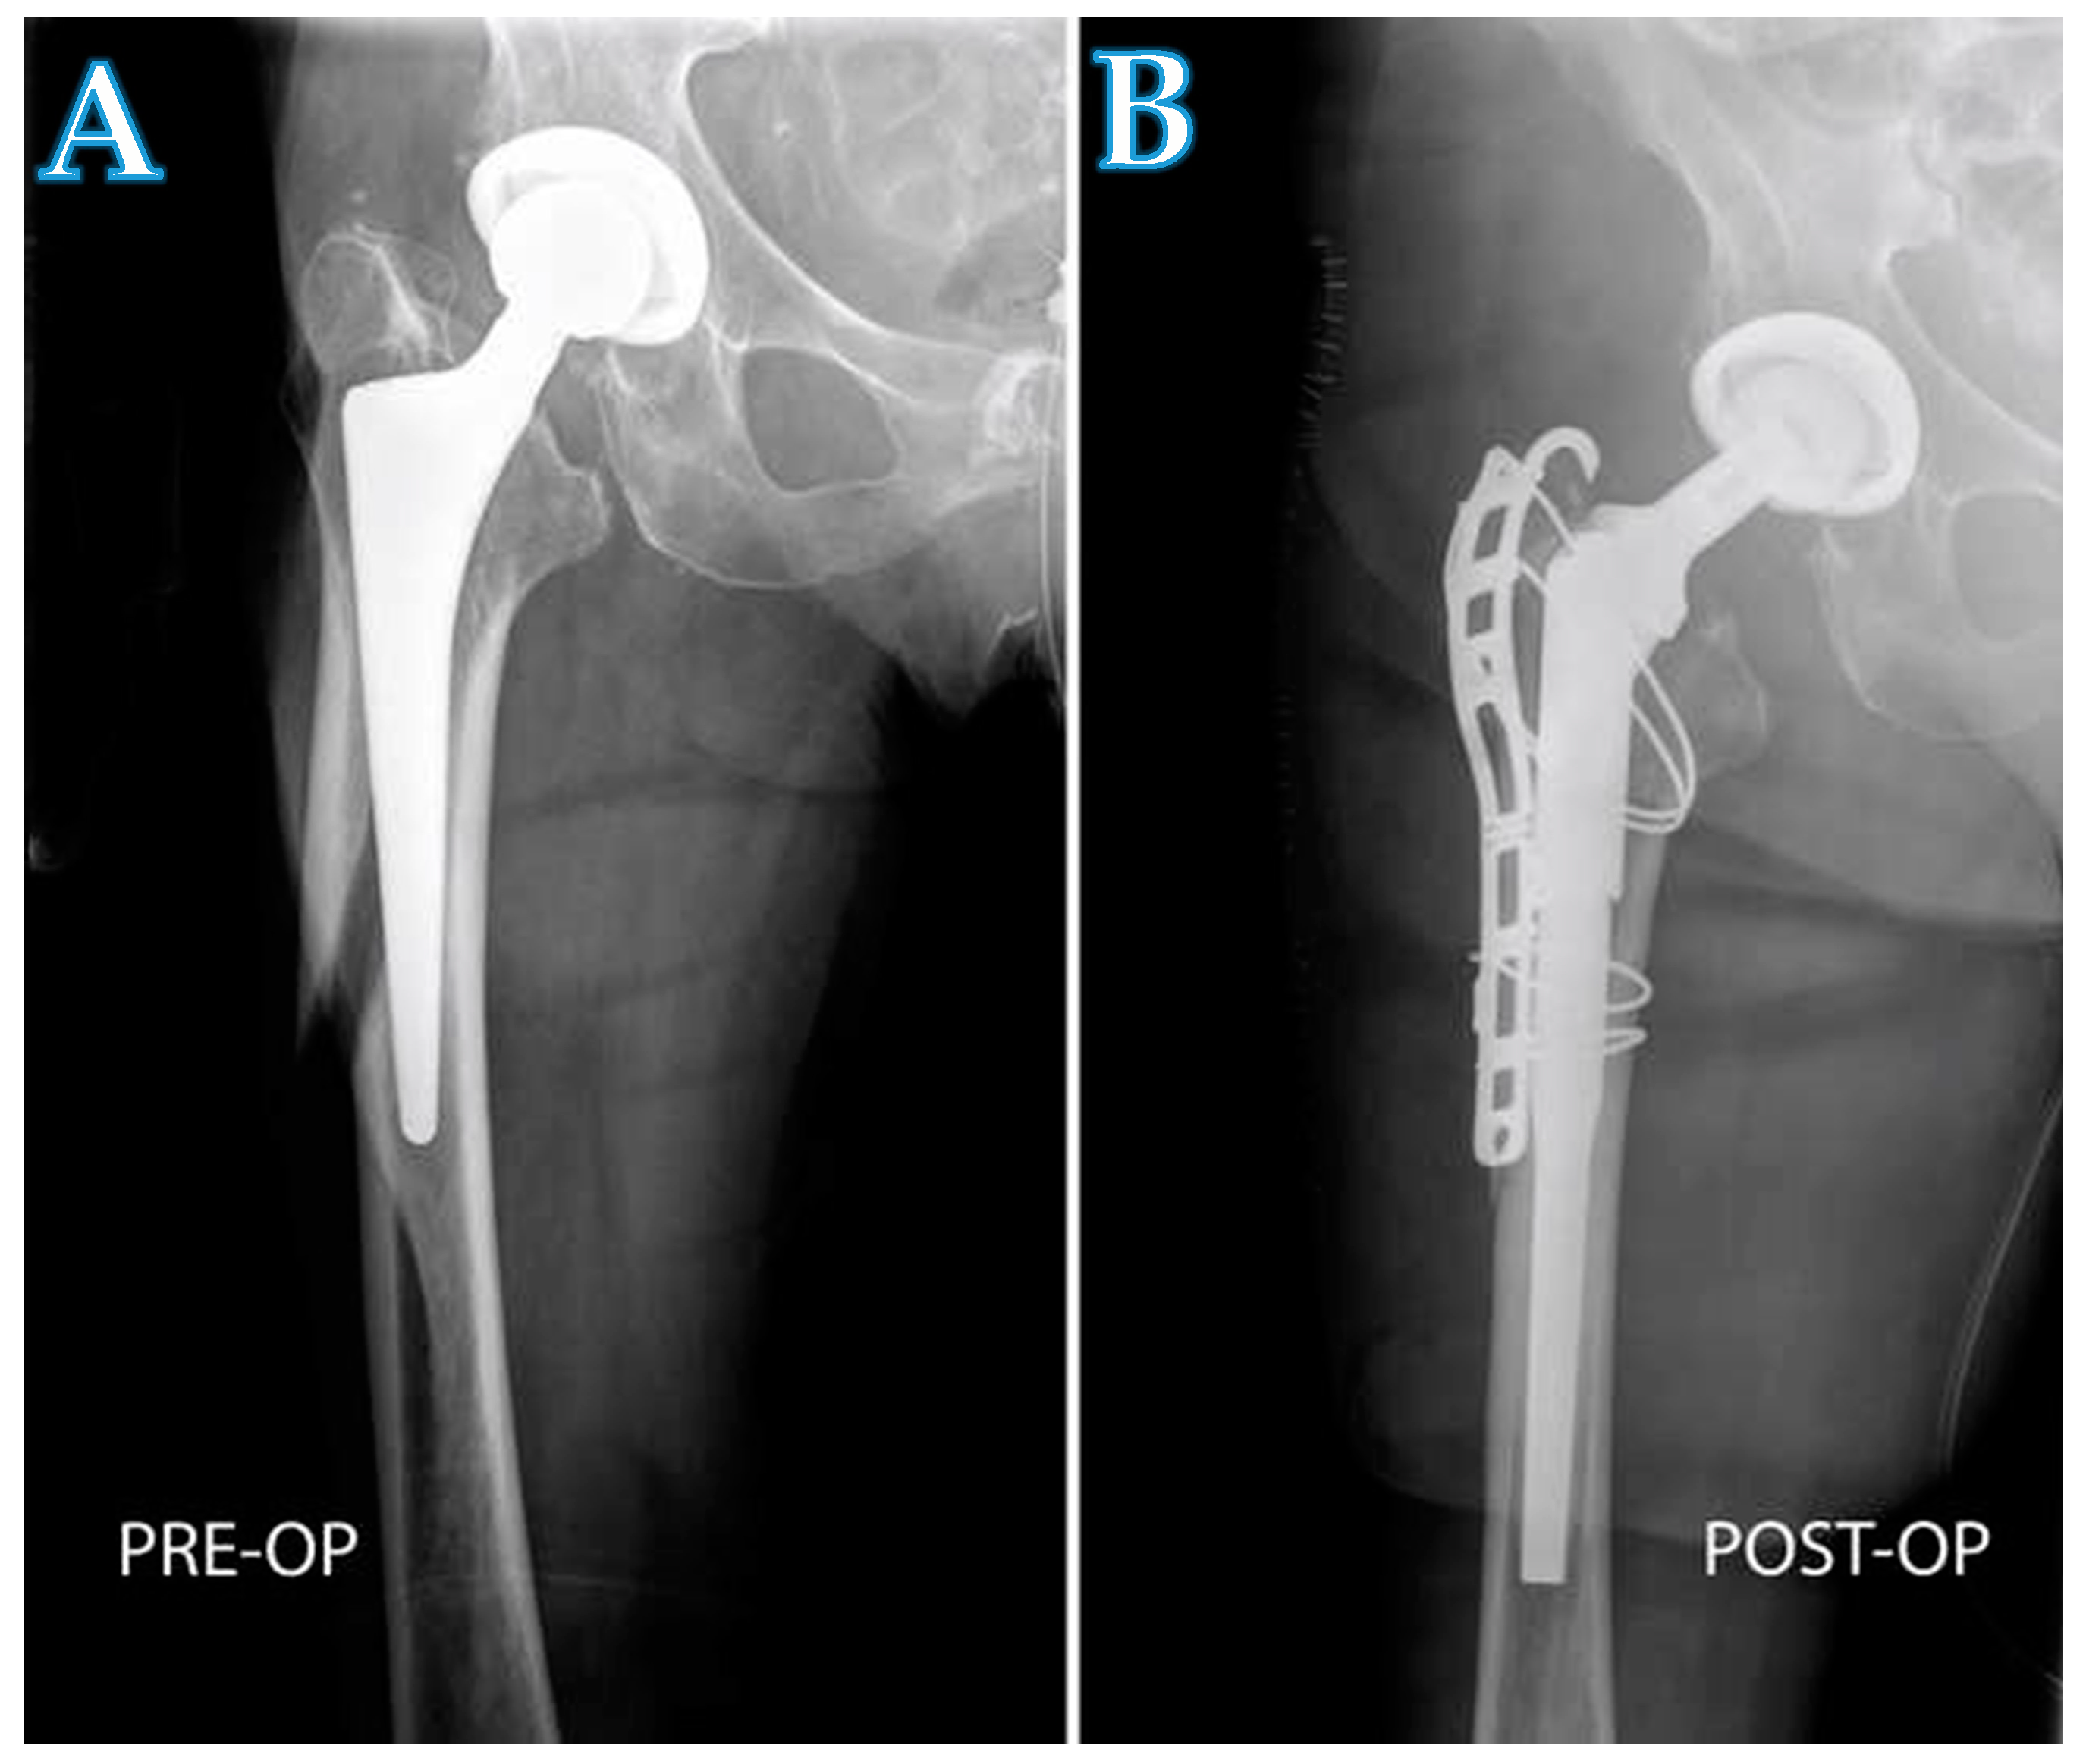

Figure 3.

A radiograph showing a patient with a periprosthetic fracture (A), and the same patient after being treated with a modular stem (B). The implantation of the long modular stem and the reduction of the fracture was performed with a proximal and distal extension of the DAA.